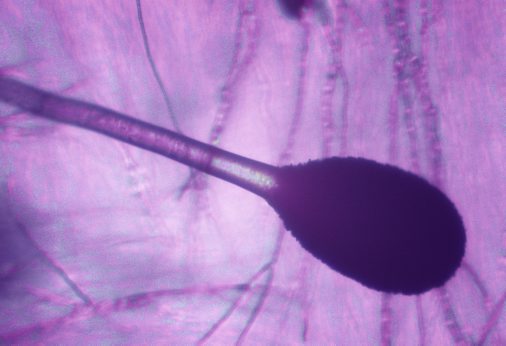

Невидимая угроза распространяется по Европе: Погибнуть от грибка-убийцы могут девять миллионов человек

Невидимая угроза распространяется по Европе: Погибнуть от "грибка-убийцы" могут девять миллионов человек

Потепление климата в Европе грозит распространением новой невидимой угрозы. Погибнуть от "грибка-убийцы" могут девять миллионов человек. Исследователи выяснили, для кого он опасен.

Жителей Европы предупредили о новой малоизвестной, но очень серьёзной угрозе. По континенту может распространиться невидимый убийца. Учёные из Манчестерского университета предупреждают: климатические изменения способствуют росту грибковых инфекций, прежде всего вызванных Aspergillus fumigatus.

Этот грибок может быть смертельно опасен для людей с ослабленным иммунитетом, а также тех, кто недавно перенёс тяжёлые вирусные заболевания. По оценкам исследовательской группы, около 9 миллионов человек на территории Европы подвержены риску заражения. По данным Independent, ареал распространения грибка будет постепенно сдвигаться с юга на север.

Aspergillus обитает в почве, на гниющих растениях и даже в бытовой пыли. Для здоровых людей он не опасен - иммунитет легко справляется с его спорами. Но у пациентов с онкологией, диабетом, болезнями лёгких или после COVID-19 грибок может вызвать тяжёлую форму аспергиллёза. Особенно тревожно то, что климатические условия способствуют его распространению и мутациям.

Уже сейчас в Европе фиксируются штаммы, устойчивые к основным противогрибковым препаратам. По словам учёных, виной тому чрезмерное использование фунгицидов в сельском хозяйстве, особенно в Испании и Италии, где такие вещества активно применяются на виноградниках и фруктовых плантациях.

Фото: ©/Globallookpress

Проблема в том, что заболевание часто протекает скрыто, без выраженных симптомов вроде кашля или одышки. И когда больной обращается за помощью, поражение может быть уже критическим. Именно поэтому специалисты настаивают: грибковые инфекции должны быть включены в европейские программы мониторинга наравне с бактериальными и вирусными угрозами.